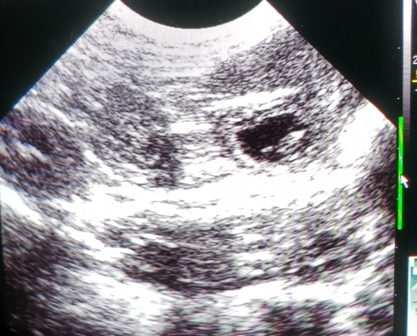

Wie schnell sie auch insgesamt wachsen, könnt ihr hier sehen:

Ich konnte mich nicht zurückhalten und musste heute noch einmal nachsehen :)

Franzi und ich haben viele Fruchtblasen, muntere Babys und schlagende Herzchen gesehen!

Zählen war unmöglich, wie ihr auf dem dritten Bild sehen könnt,

haben sich manchmal an einem Platz fünf Fruchtblasen geöffnet :O

Oft lagen zwei dicht nebeneinander, wie auf dem letzten..

Wir sind sehr gespannt!!!